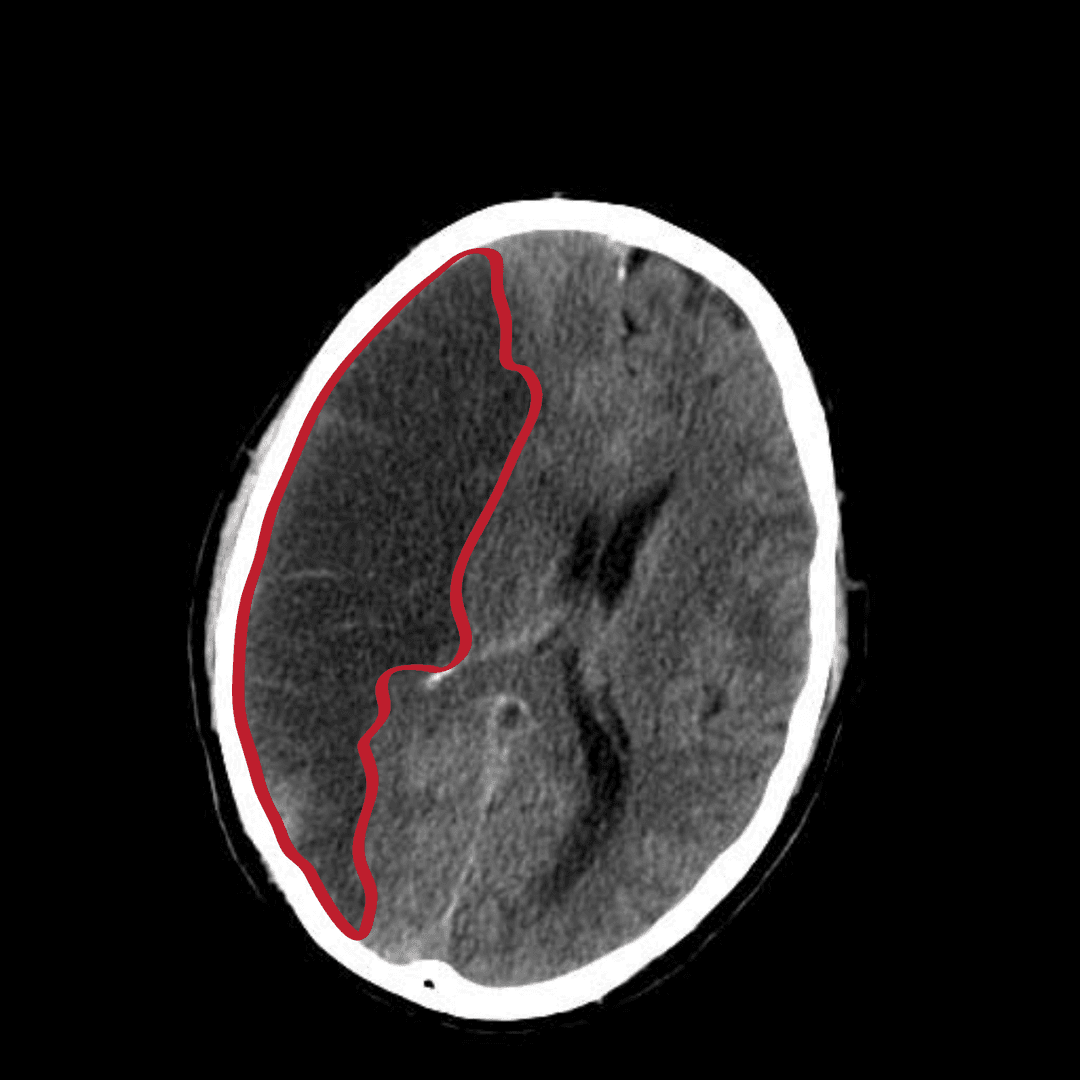

L’infarctus cérébral, appelé aussi accident ischémique cérébral, est un type d'accident vasculaire cérébral. C'est un déficit neurologique soudain d'origine vasculaire causé par un infarctus au niveau du cerveau. L'origine de l'infarctus (c'est-à-dire le mécanisme qui a conduit à l'obstruction du vaisseau sanguin) est dû dans la plupart des cas à une des raisons suivantes : thrombose (caillot de sang) apparaissant directement dans un vaisseau en amont du cerveau ; embolie dans une petite artère. Il s'agit de matériel venant d'ailleurs et obstruant la petite artère, par exemple les morceaux de sang coagulé qui se sont détachés d'une artère en amont ; sténose dans une artère. Il s'agit d'une artère qui à un endroit s'est rétrécie par un phénomène mécanique ( compression, écrasement) ou par un changement de l'état de ses parois (épaississement, rigidification, contraction, dilatation). La sténose athéromateuse d'une artère est un rétrécissement (sténose) due à une plaque d'athérosclérose. Il existe des sténoses par compression extrinsèque (par exemple tumeur qui comprime le vaisseau) et des plaques d'athérome non sténosantes (au début de la maladie). Selon la durée des symptômes, on définit : l'accident ischémique transitoire (AIT) : les AVC ischémiques totalement régressifs en moins de 24 heures ; l'accident ischémique rapidement régressif : les AVC ischémiques dont les signes disparaissent en moins de 5 jours ; l'accident ischémique constitué (AIC) si les signes persistent au-delà de 5 jours. L'infarctus cérébral est causé par une diminution voire un arrêt brutal du débit sanguin dans les branches du réseau vasculaire alimenté par un vaisseau (en général une artère) subissant un blocage partiel ou total (par thrombose, embolie, sténose, ou autre cause pas toujours identifiable). Ainsi, les cellules nerveuses alimentées par ces branches sont privées soudainement d'oxygène et de sucres, ce qui provoque en quelques minutes leur détérioration ou leur mort.